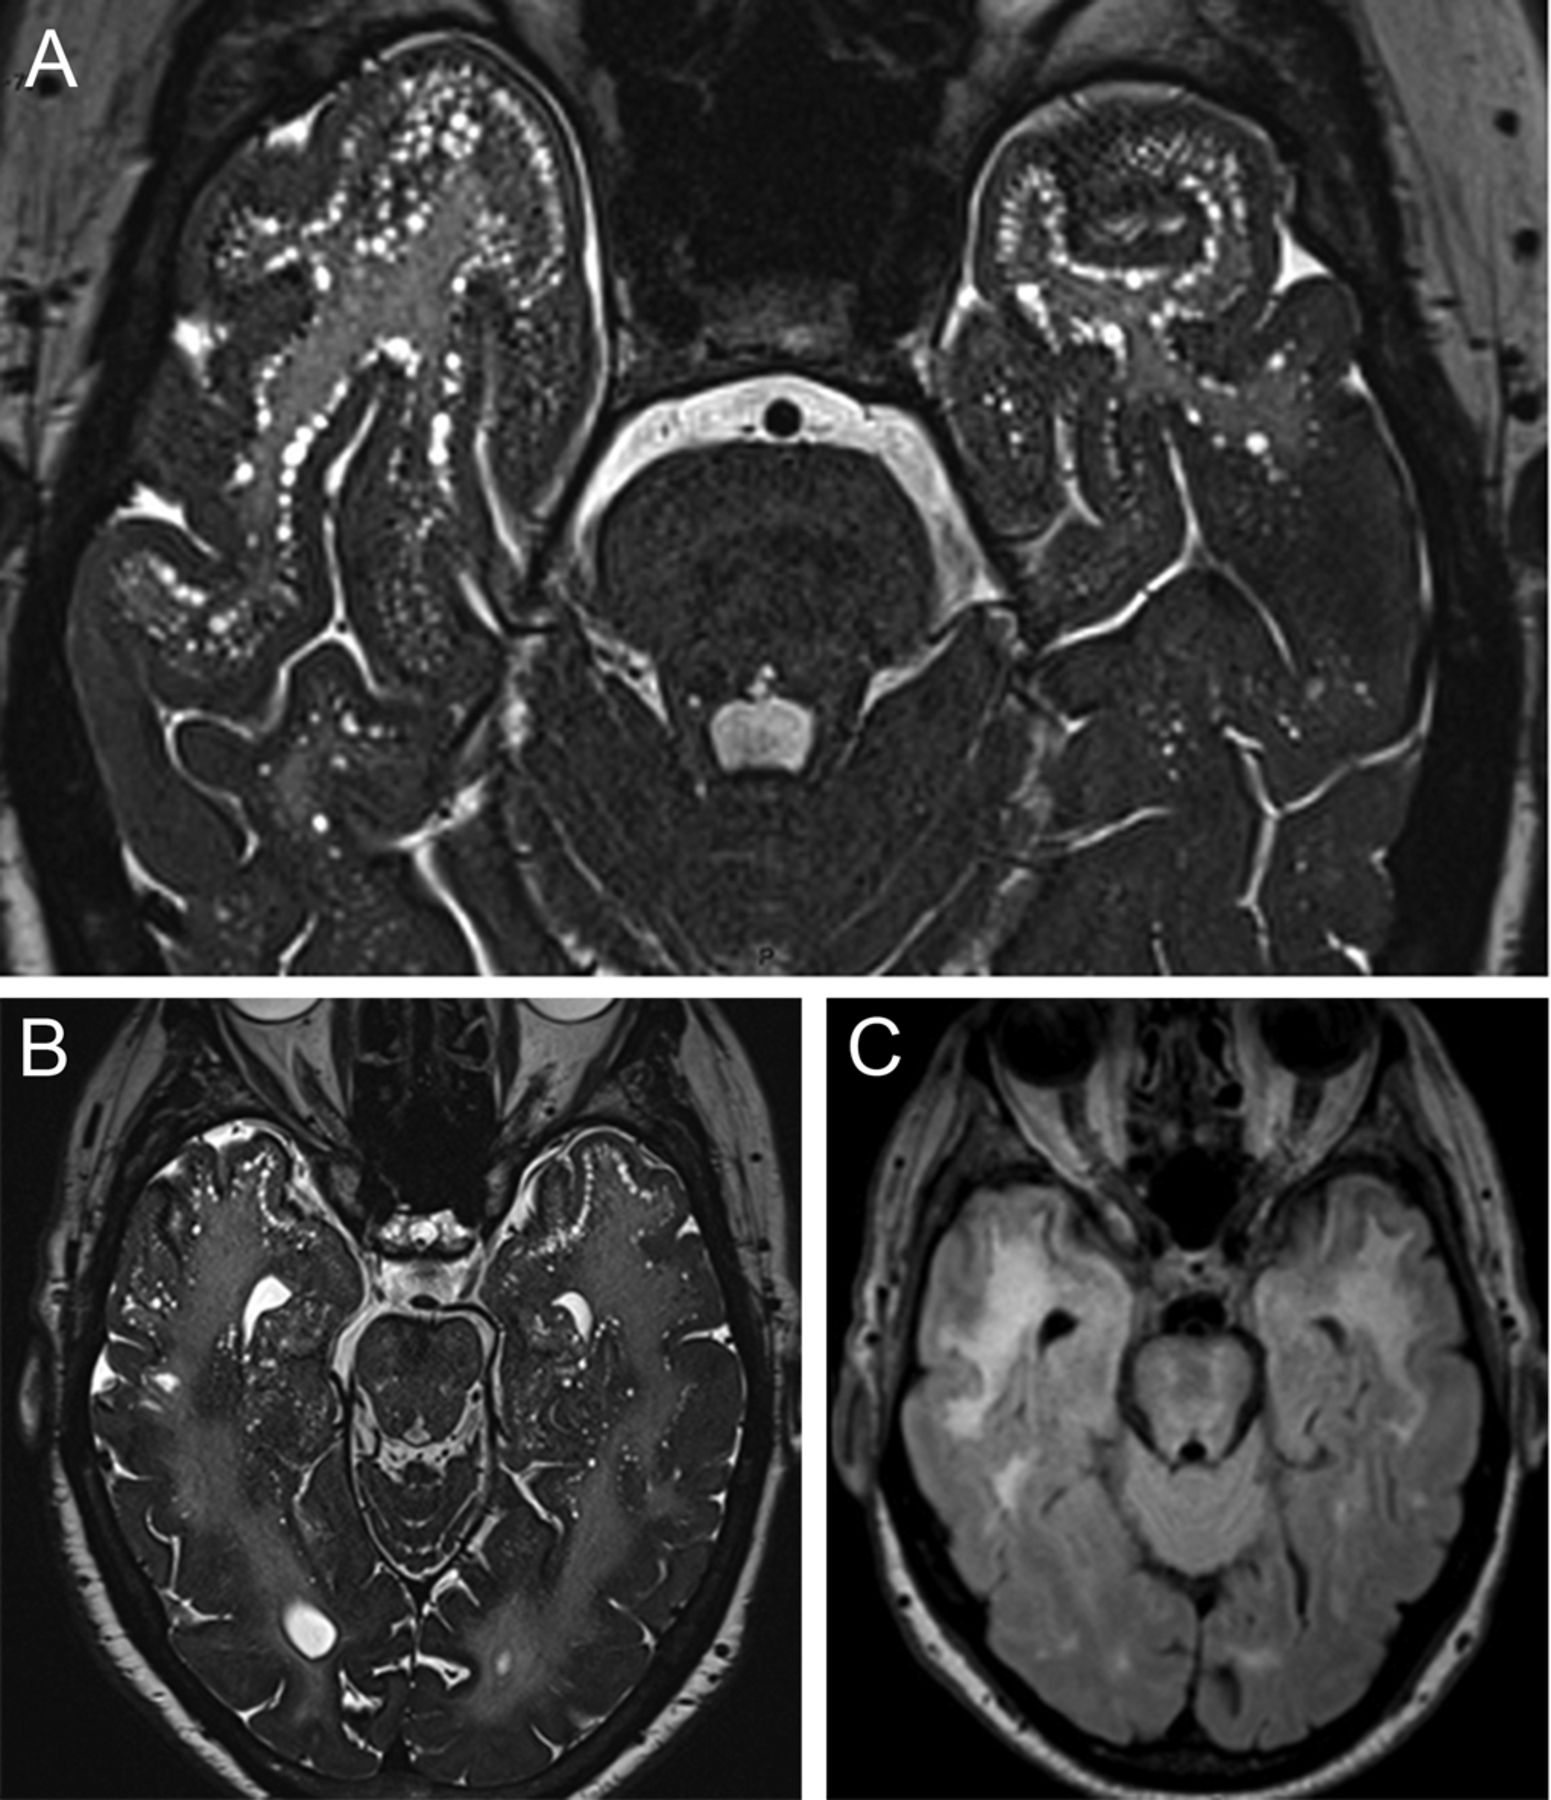

两个脑患者常染色体显性与皮层下梗死和脑白质病动脉病(CADASIL) (图),进化认知退化,核磁共振。海道测量三维高分辨率涡轮旋转回声(谢霆锋)变量翻转角度序列(空间)进行演示皮层下血窦病变(sll) (图中,A和B在CADASIL)被认为是特定的。1

患者的脑部MRI脑常染色体显性遗传与皮层下梗死和脑白质病动脉病(CADASIL)显示hyperintense病变fluid-attenuated反转恢复(C)与众多颞叶皮层下血窦病变,最好以一个3 d空间序列(a, B)。

空间是一个3 d谢霆锋序列类似于其他水文序列,在水和脂肪有很高的信号,让优秀的对比CSF和其他结构;sll表现为线性排列组圆形,外切结病变的灰色和白色物质与脑脊液信号强度相似,1主要分布在前颞叶。